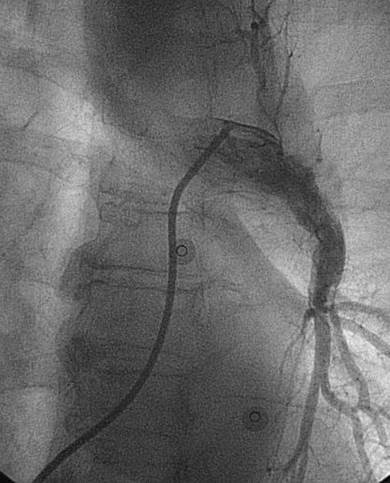

Trombectomía de arteria pulmonar izquierda

Angiografía de la arteria pulmonar izquierda realizada con un catéter en espiral de 6 F en ángulo, que demuestra la presencia de un trombo de gran tamaño dentro de la arteria pulmonar izquierda y en las bifurcaciones lobulares intermedia e inferior.

Se efectuó una trombectomía reolítica con el catéter PE de AngioJet® mediante un catéter guía multifunción de 8 F a través de una guía de angioplastia hidrófila de 0,035’’.

Angiografía pulmonar izquierda realizada tras una trombectomía reolítica en la que se muestra la mejora del índice de perfusión y obstrucción.